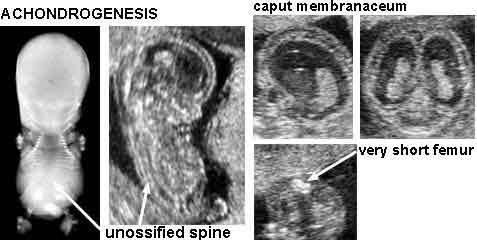

Achondrogenesis

What is the second most common form of lethal dwarfism?

Achondrogenesis

What is Achondrogenesis?

rare lethal form of short limbed dyplasia

severe malformation of bones and cartilage. Babies usually still born or die shortly

What is the sonographic appearance of Achondrogenesis?

demonstration of the triad

severely shortened limbs

lack of vertebral ossification

large head with slightly decreased ossification